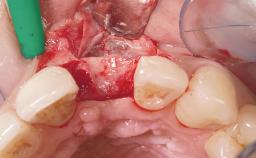

A 33-year-old female patient presented with an upper left central incisor that required extraction after a failed endodontic therapy. The tooth had been traumatized when the patient was a teenager and had undergone several endodontic treatments, including two apicectomy procedures. The patient was in good health and did not smoke. Clinical examination showed that the patient had a high lip line. In full smile, the gingival margins of the upper teeth were visible to the first molars. The gingival margins of central incisors 11 and 21 were only just showing. Examination of tooth 21 confirmed that the tooth was mobile and had hypererupted by 1 mm.

Placement Protocol Immediate implant placement

Tooth Site Maxillary incisor or canine

Socket Morphology Single-root socket

Socket Integrity Damage to one or more bone walls

Bone Volume Damage to one or more socket walls